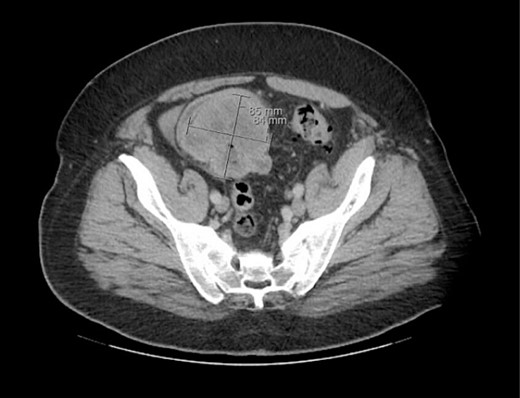

A 53-year-old male presented to the emergency department (ED) with complaints of persistent right sided abdominal pain, nausea, and vomiting for several weeks. He was initially seen at an Urgent Care and was diagnosed with gastroenteritis. His past medical and surgical history was significant for type two diabetes mellitus, history of deep vein thrombosis anticoagulated with aspirin 325 mg daily, horseshoe kidney status post right nephrectomy, and gout. In the ED his vitals were heart rate 100 bpm, respiratory rate 20, blood pressure 113/75, SpO2 99%, and temperature of 37.5 C. Physical exam was significant for abdominal tenderness in the right upper and lower quadrants, negative for costovertebral angle tenderness bilaterally, and negative for peritoneal signs. The ensuing work up showed a positive fecal occult blood test and abdominal X-ray showing air-filled loops of small bowel measuring 4.8 cm in cross-section, concerning for small bowel obstruction. There was no free air and a moderate colonic stool burden. A computed tomography (CT) abdomen was ordered to further characterize the small bowel obstruction revealing a necrotic mass in the right lower quadrant. The surgical team was consulted and the patient was admitted for treatment.

The patient was initially managed nonoperatively with conservative measures including nasogastric (NG) tube decompression, pain control, and serial abdominal exams. Surgery was consulted once CT imaging was obtained (Figs 1–3) and recommended that the patient undergo surgery to resect the identified mass and relieve the obstruction. During the surgical exploration, a mass originating from the terminal ilium was identified that was densely adhered to the peritoneum, bladder, and sigmoid colon, requiring careful dissection. The mass, three lymph nodes, and 29 cm of associated small bowel segment was resected with grossly negative margins, with the mass measuring 7 cm × 8 cm × 9.5 cm. A side-to-side anastomosis was created and the specimens were sent to pathology for further investigation. Postoperatively the patient was hospitalized for 7 days for pain control and monitoring. On postoperative day eight he was discharged with follow up appointments with oncology, general surgery, and a referral to an academic cancer center.

Initial CT imaging, axial cut, showing necrotic mass causing small bowel obstruction.